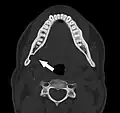

Stafne bone cavity seen on axial CT

Stafne's defect is usually discovered by chance during routine dental radiography.[11] Radiographically, it is a well-circumscribed, monolocular, round, radiolucent defect, 1–3 cm in size, usually between the inferior alveolar nerve (IAN) and the inferior border of the posterior mandible between the molars and the angle of the jaw. It is one of the few radiolucent lesions that can occur below the IAN. The border is well corticated and it will have no effect on the surrounding structures. Computed tomography (CT) will show a shallow defect through the medial cortex of the mandible with a corticated rim and no soft tissue abnormalities, with the exception of a portion of the submandibular gland. Neoplasms, such as metastatic squamous cell carcinoma to the submandibular lymph nodes or a salivary gland tumour, could create a similar appearance but rarely have such well defined borders and can usually be palpated in the floor of the mouth or submandibular triangle of the neck as a hard mass. CT and clinical exam is typically sufficient to distinguish between this and a Stafne defect. The Stafne defect also tends to not increase in size or change in radiographic appearance over time (hence the term "static bone cyst"), and this can be used to help confirm the diagnosis.[11] Tissue biopsy is not usually indicated, but if carried out, the histopathologic appearance is usually normal salivary gland tissue. Sometimes attempted biopsy of Stafne defects reveals an empty cavity (possibly because the gland was displaced at the time of biopsy), or other contents such as blood vessels, fat, lymphoid or connective tissues. Defects of the anterior lingual mandible may require biopsy for correct diagnosis at this unusual location.[5] The radiolucent defect here may be superimposed on the lower anterior teeth and be mistaken for an odontogenic lesion. Sometimes the defect may interrupt the contour of the lower border of the mandible, and may be palpable. Sialography may be sometimes used to help demonstrate the salivary gland tissue within the bone.